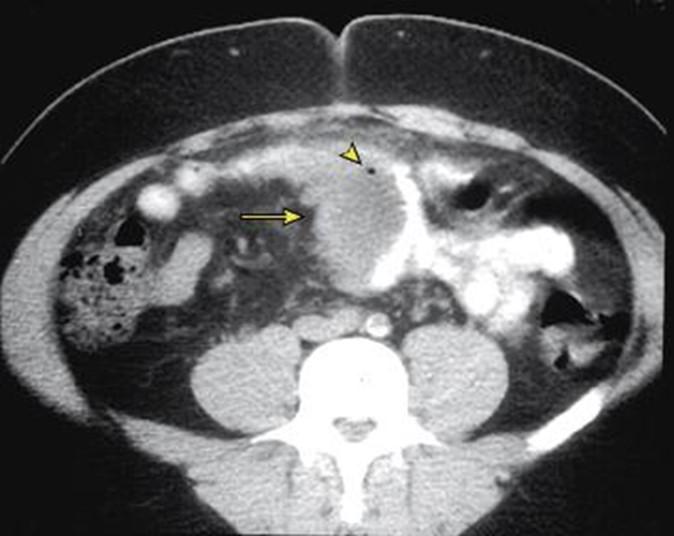

圖為憩室炎患者腹部電腦掃描圖片,情況嚴重者可引致膿瘡。